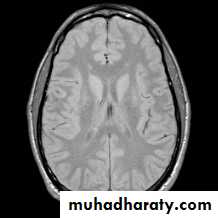

T1 WEIGHTING

A short TR and short TE will result in a T1 weighted imageExcellent for demonstrating anatomy

T2 WEIGHTING

A long TR and long TE will result in a T2 weighted image

Excellent for demonstrating pathologyMANY OTHER DIFFERENT TYPES OF IMAGES THAT COMBINE ABOVE AND INCLUDE OTHER PARAMETERS

T1-, -, and T2-weighted images

-weightedT2-weighted

T1-weighted